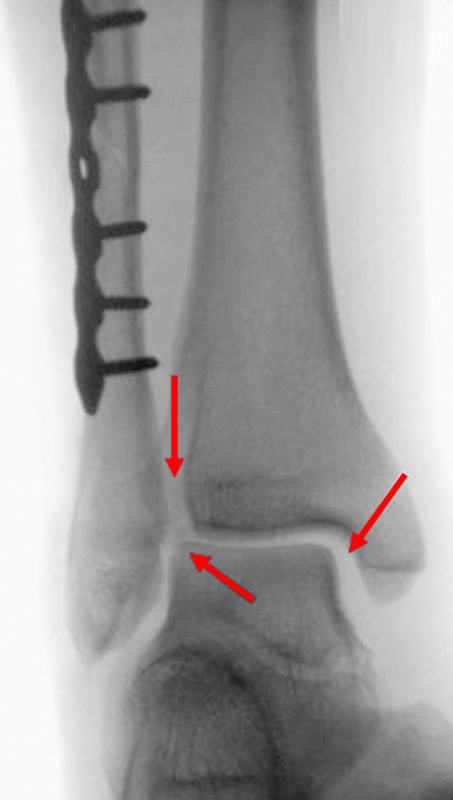

Die Standard-Röntgenaufnahmen des oberen Sprunggelenks bestehen aus drei Aufnahmen: der antero-posterioren Aufnahme (ap), der antero-posterioren Aufnahme mit Innenrotation des Unterschenkels von 20° („Mortise view“), sowie der streng seitlichen Aufnahme (siehe S2-Leitlinie Sprunggelenksfraktur). In der Röntgen-Bildgebung sollte neben den klassischen Frakturzeichen die Integrität der Syndesmose beurteilt werden. Dies erfolgt über die Beurteilung der Breite des lateralen und medialen Gelenkspalts („medial clear space“), des tibiofibularen Abstands 1cm oberhalb des OSG-Gelenkspalts („tibiofibular clear space“), bzw. der tibiofibularen Überlappung. Eine Verbreiterung des tibiofibularen Abstands über 5 mm oder die Erweiterung des medialen Gelenkspalts können Zeichen einer begleitenden Syndesmosenverletzung sein. (Abbildung 3) 6.